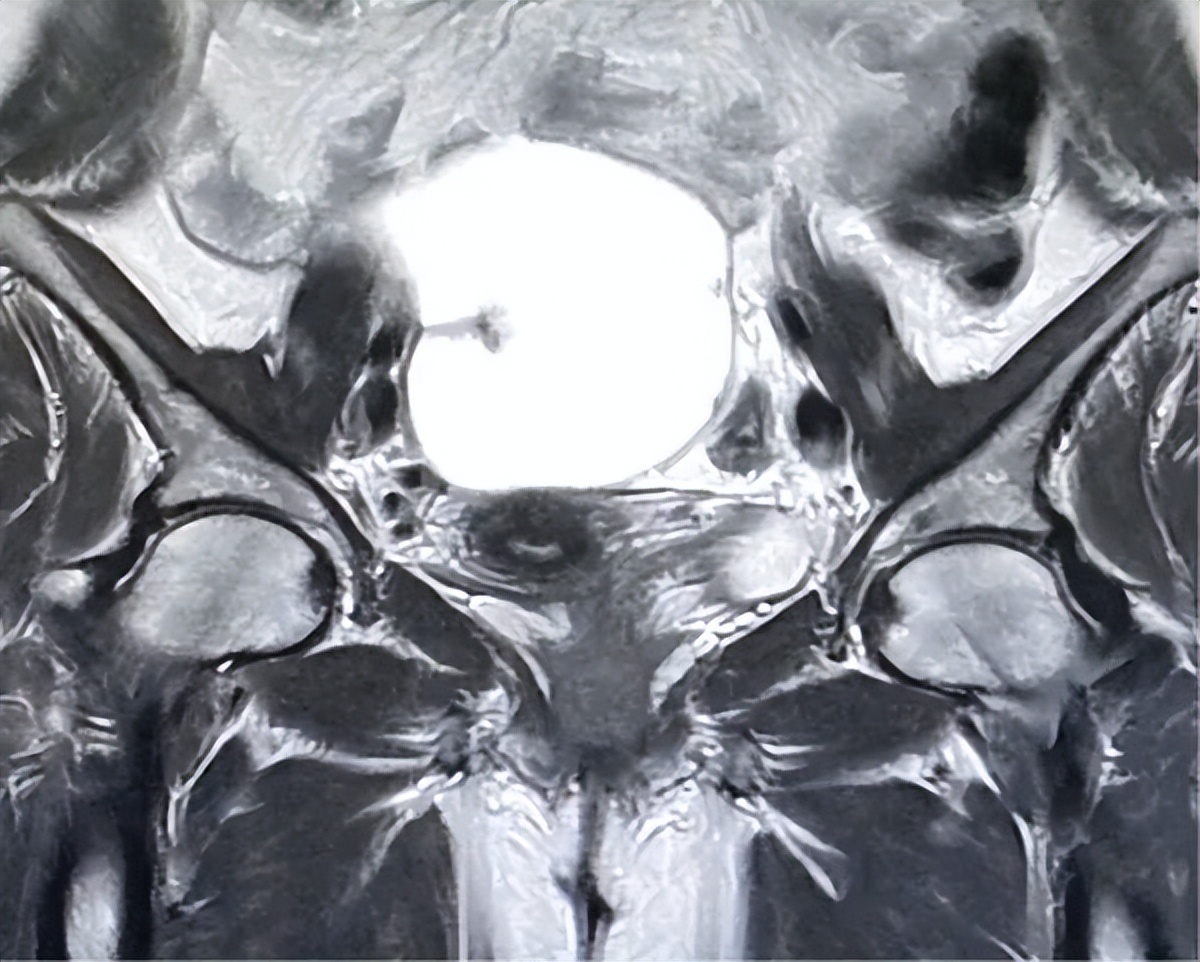

为了进一步评估病灶特征,患者进行了MRI检查,确认右侧附件区有一个边界清晰的囊性病变,大小为12×10×6 cm。病变主要为液性,表现为T1低信号、T2高信号。其内部结构为多房性,伴有少量薄而光滑的分隔,并包含一小块T1高信号、T2低信号区的病灶(在脂肪抑制序列上未被抑制),符合陈旧性出血的表现。增强扫描仅显示有薄的、轻微的分隔强化,无实性强化结节、不规则/增厚分隔(>3 mm)或坏死证据。解剖学上,囊肿与邻近盆腔结构分界清晰,无侵袭征象。基于这些特征(囊内容物为单纯液体、分隔薄而光滑、无实性成分),该病变经影像学评估为良性复杂性囊肿,如囊腺瘤或出血性囊肿(图1和图2)。

图1.增强磁共振成像显示右侧附件/卵巢有一个边界清晰的大囊性病变,大小为12×10×6 cm

图2.增强磁共振成像显示多房性病变,伴有少量薄层光滑的分隔